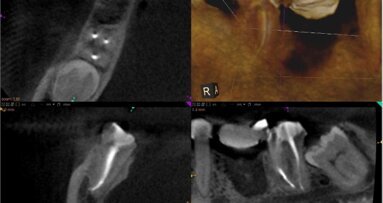

Wskaźnik powodzenia leczenia endodontycznego waha się w zakresie 85-97%. Dla uzyskania takiego poziomu niezbędne są: stosowanie właściwych protokołów terapeutycznych, wiedza oraz kontrola infekcji (Ryc. 1a-d).